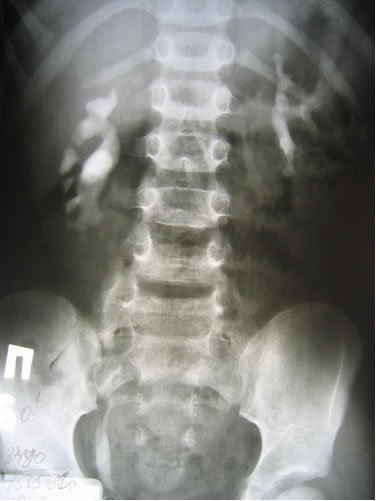

Обзорная и экскреторная урография

УЗИ - Правая почка – 8,7х3,1 см, т.п.

1,2 – 1,3 см. ЧЛС не расширена. В проекции лоханки определяется

конкремент размером 1,7 см, окруженный жидкостью до 0,3

см. Левая почка – 9,3х3,8 см, т.п. 1,3 см. ЧЛС не расширена.